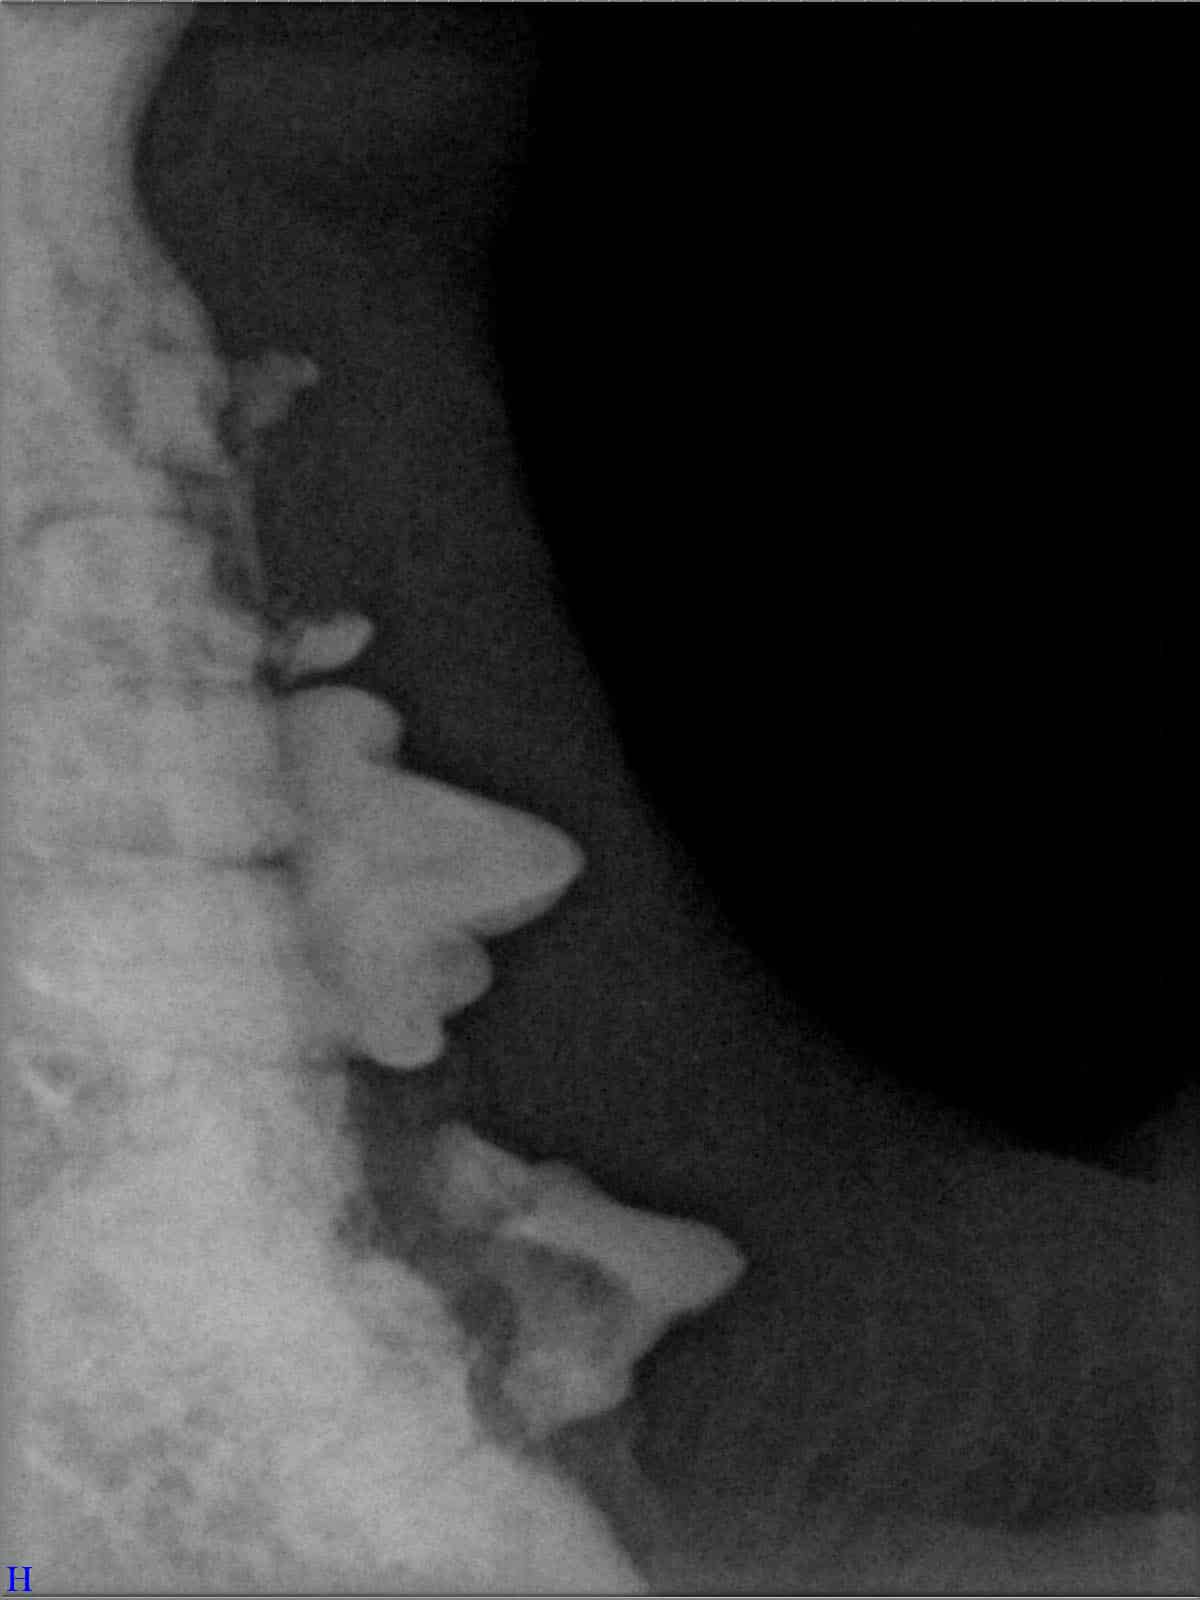

Ein entscheidender Baustein der FORL-Diagnostik ist das dentale Röntgen. Viele Läsionen sind von außen nicht sichtbar und lassen sich ausschließlich mithilfe moderner Röntgentechnik erkennen. In der Hamburger Praxis kommt digitales Dentalröntgen zum Einsatz, das detailreiche Aufnahmen bei geringer Strahlenbelastung ermöglicht. So kann FORL bereits in frühen Stadien diagnostiziert werden.

Das sehen Sie von außen – so sieht es auf den Röntgenbildern aus.

FORL Katze Röntgenbild

Röntgenbilder